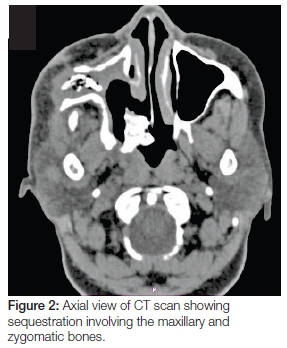

A 55 year old female with a medical history of hypertension and type II diabetes was referred to the Maxillofacial and Oral Surgery Clinic, Grey's Hospital, South Africa. The patient presented with a right unilateral facial swelling with pus discharging through three cutaneous fistulae in the right zygomatico-orbital region, the lesion being of three years duration (Figure 1). The patient had undergone a maxillary sequestrectomy performed three years ago by the Department of Otolaryngology. This was done in an attempt to treat her chronic suppurative sinusitis, which had eroded her maxillary sinus walls and hard palate (Figures 2 & 3). She had received several doses of antibiotics including a Penicillin derivative such as Amoxicillin combined with Clavulanate, an Imidazole such as Fluconazole, a Tetracycline such as Doxycycline and a Nitroimidazole such as Metronidazole on separate occasions spanning the three year period.

The records of the patient did not reveal whether investigations for microbial culture and sensitivity were done. It was therefore presumed that antibiotics were administered empirically. The discharging sinuses had not resolved with the antibiotic treatment. Several computed tomography (CT) views, recorded at the time of attendance at the MFOS Clinic, confirmed the presence of a circumscribed mixed radiopaque/radioluscent lesion, 1.4 cms in diameter, within the body of the zygomatic bone extending from the region of the right lateral antral wall to the infero-lateral orbital margin. The lesion contained a hypodense cortex with multiple air loculi within and around it, an appearance in keeping with the features of a sequestrum (Figure 4). A provisional diagnosis of chronic suppurative osteomyelitis was made.